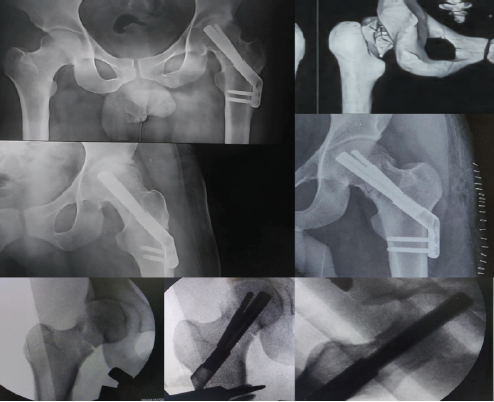

Case 5

A 35-year-old male with intellectual disability sustained a displaced Garden’s type IV, Pauwel’s type II fracture. Fixation was performed with the FNS, but with only a single unicortical distal locking screw at the level of the cancellous lesser trochanter, and the anti-rotation screw locking mechanism failed, leading to backout. By 15 months, radiographs showed radiolucency and reactive bone formation around the implant, though infection was excluded clinically and with laboratory investigations. The radiographs also revealed generalized osteopenia with thinned out femoral diaphyseal cortices. A Bone Mineral Density scan was done which also revealed osteopenia (T-score – 1.8) (Fig. 4). Hence, factors that might have contributed include poor bone quality, mechanical insufficiency due to unicortical fixation, and possible abnormal femoral version and early weight-bearing on the patient’s side. The patient is now being counseled to undergo a total hip replacement.

Figure 4: Top left: Pre-operative radiographs of Case 5; Bottom row: immediate post-operative radiographs; top right: follow-up radiographs at 15 months showing fixation failure, non-union, and screw backout.

Case 6

A 34-year-old male sustained a high-energy femoral shaft fracture with a concomitant low-energy, undisplaced, basicervical Garden’s type I, Pauwel’s type II femoral neck fracture. The neck fracture was stabilized anatomically in situ with compression using the FNS, with good implant positioning but a slightly lower tip-apex distance. At 5 months, the femoral neck had united (confirmed with computed tomography) (Fig. 5), but the shaft fracture had gone into non-union, for which exchange nailing and grafting were planned.

Figure 5: Radiographs (left) and computed tomography (top right) confirming complete fracture union in Case 6. Bottom center and right: immediate post-operative radiographs.